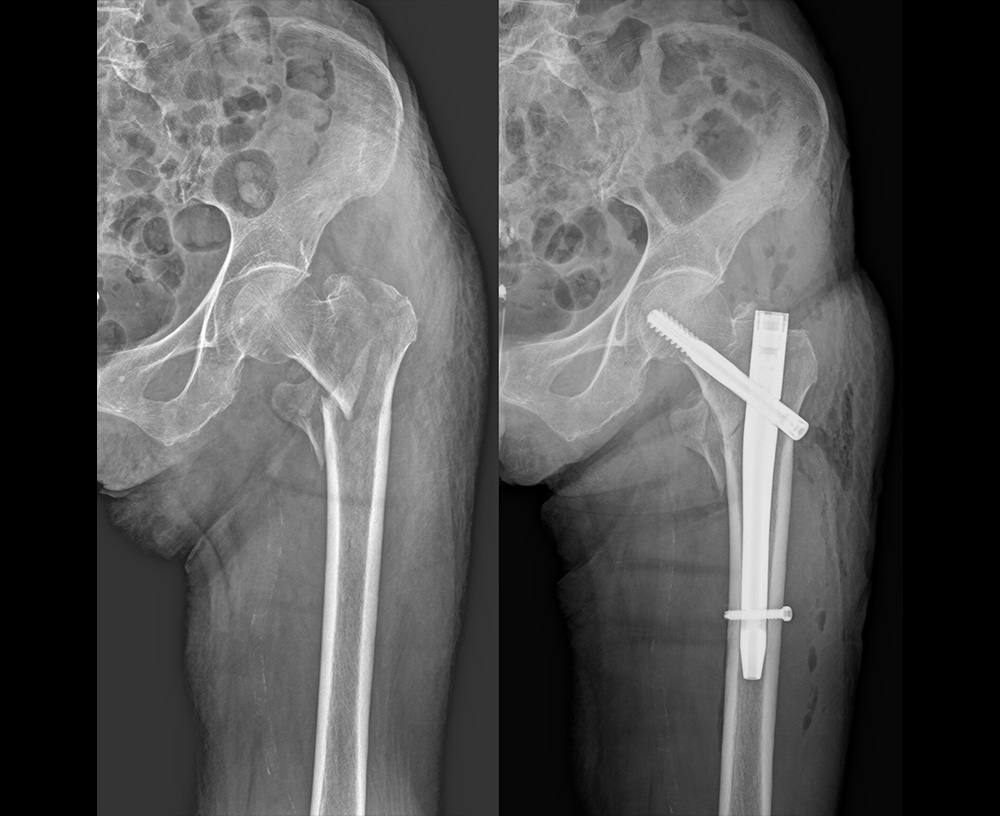

高齢者の方々によく起こる大腿骨頚部骨折(図1・図2)、肩から上腕の骨折(図3)、手関節周囲の骨折(図4)、人工膝関節置換術(図5)などの手術を行っております。

骨折観血的手術

図2:骨折観血的手術